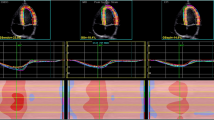

Fig. 4

figure 4

Myocardial performance response during exercise as measured by mean LV peak systolic longitudinal (Sl) and circumferential (Sc) strain and strain rate (SRl, SRc), respectively. Letters above each stage show statistical significant difference (ANOVA and post-hoc test) in comparison with the selected exercise stage, such that letters correspond to: b = 0 W, c = 50 W, d = 100 W, e = 150 W, f = 2 min rec and g = 6 min rec; (e.g. in left upper panel at baseline significant differences found compared to 0, 50, 100, 150, 2 min rec and 6 min rec)

LV myocardial performance during exercise—2-D strain